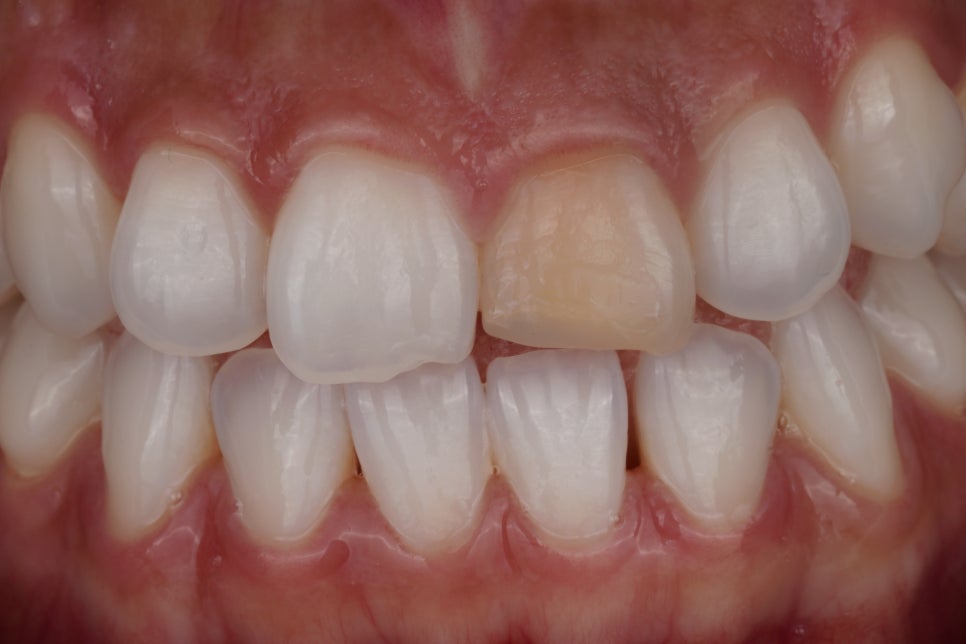

앞니 하나만 색깔이 이상해요.

어느 날 셀카를 찍었는데 유독 앞니 하나만 멍든 것처럼 어둡게 보여 발견하시는 경우가 대부분인데요ㅎㅎ

충치가 생긴 것도, 치아가 깨진 것도 아닌데 혼자만 회색빛으로 겉도는 앞니.

거울을 볼 때마다 시선이 꽂히고, 웃을 때 자기도 모르게 입을 가리게 되죠.

어릴 때 넘어지면서 부딪히거나 외상 받은 경험이 있으시거나 신경치료를 받은 적이 있으시다면 안쪽에서부터 '변색'이 진행되고 있는 것입니다.

오늘은 앞니 신경치료 후 색이 변하는 원인과 치료 방법인 실활치 미백 이야기를 해보려고 합니다.